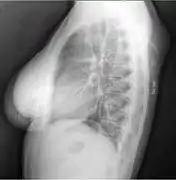

A physical exam is typically the easiest way to diagnose it. Rarely, a tissue biopsy or imaging may be required. The imaging modality of choice is magnetic resonance imaging (MRI), because it has superior sensitivity of distinguishing it from liposarcoma as well as mapping the surrounding anatomy.[20]

X-ray showing lipoma